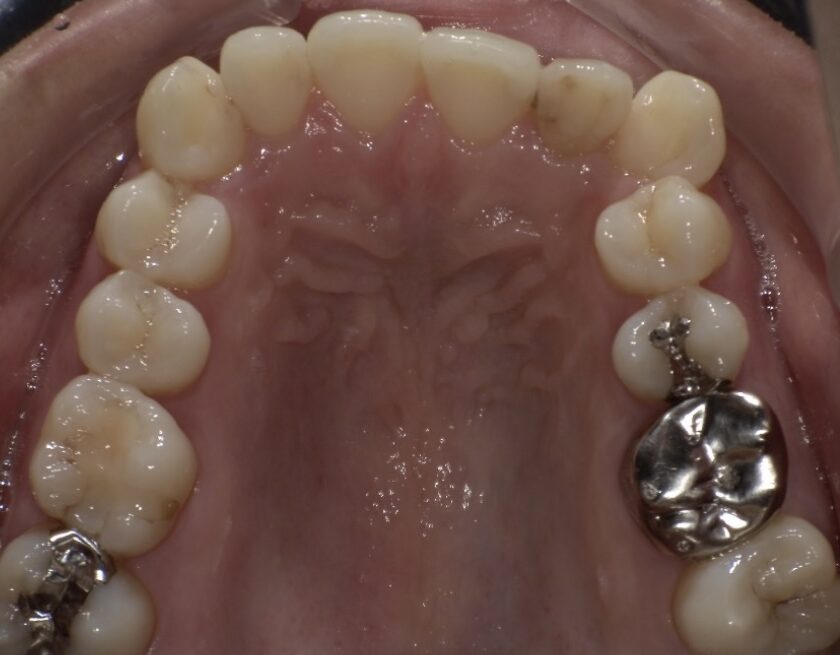

今回ご紹介するのは、前歯の出っ張り(上顎前突)とガタガタ(叢生)を気にされて来院された20代女性の患者様です。

最初に来られた際の写真です。上の前歯が前側にありますが内側を向いており、前歯の噛み合わせが深い状態であり、ガタガタもあります。